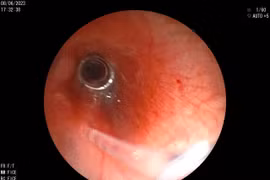

Các bác sĩ khoa Tai Mũi Họng – Bệnh viện Sản Nhi Nghệ An cho biết, khoa vừa tiến hành nội soi gắp dị vật là một cục pin nhỏ ra khỏi đường thở cho một bệnh nhi 8 tháng tuổi.